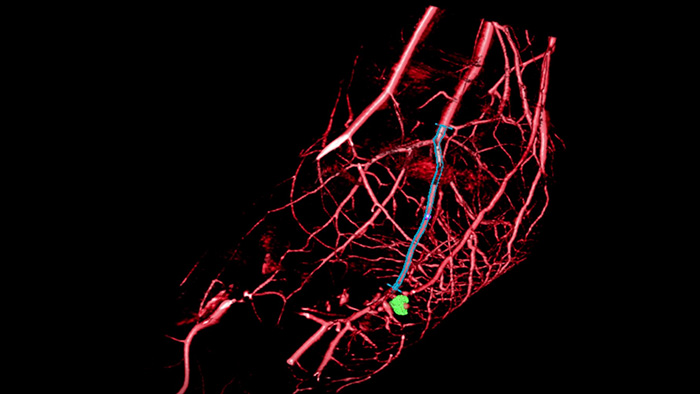

VesselNavigator provides an intuitive and continuous 3D roadmap based on existing CTA and MRA datasets to guide you through vasculature during peripheral procedures.

SmartCT Roadmap overlays a 3D reconstruction using SmartCT Angio or SmartCT Soft Tissue, to emphasise target vessel and lesions, aiding guidewire and catheter navigation through complex vessel structures. All controlled via the touch screen at the table.